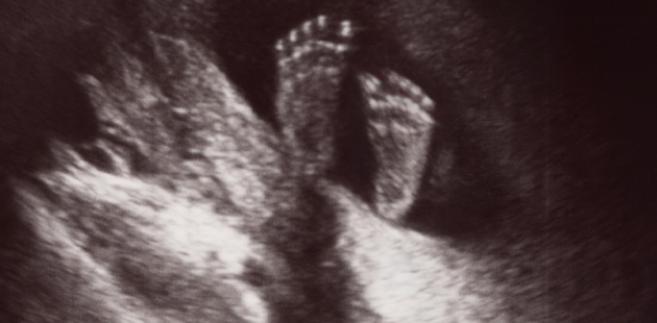

Не очекувале дека ќе го видат ова на преглед: Бебе буквално си игра во матката

Кога родителите отишле на преглед воопшто не очекувале дека ќе го видат ова. Малото бебе се оттурнува со стопалата од ѕидот на матката и се ниша напред-назад. Не е невообичано за бебињата да се занимаваат самите себе во матката, го смукаат палецот или прават салта, но оваквите игри ретко се снимени на утразвук. Прекрасно е и восхитувачки.